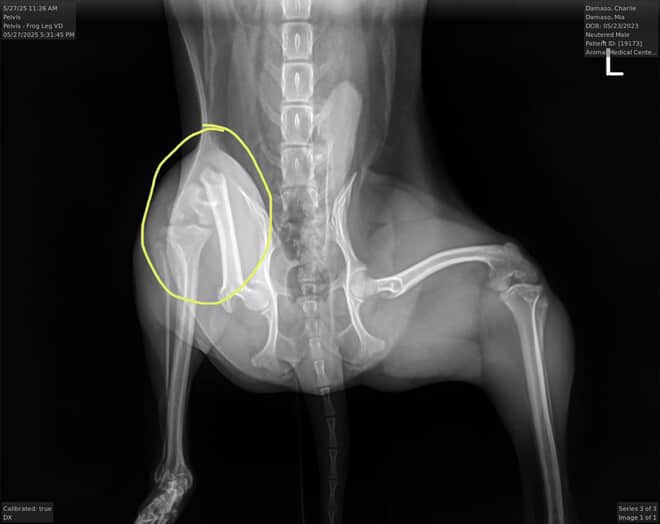

Hello everyone and thanks for taking the time to read this! The reason I’m creating this GoFundMe account is because Charlie, my niece's chihuahua, was accidentally hurt at the hands of my 6 y/o son. His leg ended up being broken and the vet says he needs surgery.